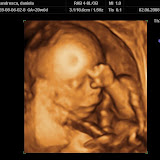

Cica se facea ca eram inchis intr-o cutie mica, care cu timpul s-a largit. Nu am realizat ca eu defapt cresteam si o largeam din ce in ce mai tare. Ma scaldam intr-un lichid toata ziulica, ma jucam cu manutele, cu piciorusele si imi placea, mai ales, sa dorm. Astfel ca-i dadeam adesea emotii lui mami, care se gandea ca poate am patit ceva.

Ce ma mai agitam, plin de bucurie, cand auzeam vocea mamei cantandu-mi bland sau dandu-mi cate un ghiont ca sa ma trezesc. Desi eu eram treaz de mult dar mi-era lene sa fac valva in jurul meu. Hmm, defapt nu-mi placea sa fiu in centrul atentiei de pe atunci. Aveam treburi serioase, domne, acolo in cutie, decat sa starnesc spiritele! Insa intr-o zi m-am decis sa nu mai stau cu capul in jos si m-am intors. Sa vad cutia si din alt unghi. Ma plictisisem, la naiba! Mami insa era ingrijorata. Simteam eu asa prin cutia aia ca ea nu mai avea stare. Dar n-a durat mult pana m-am trezit ca nu mai ma scald in piscina mea de acasa. Si, la putin timp dupa asta, am iesit afara la lumina.